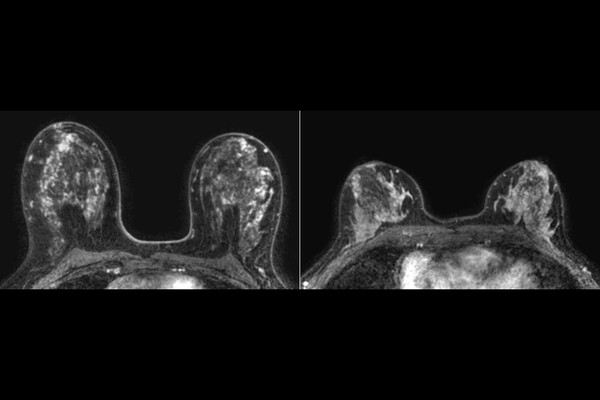

В экспериментах на мышиных моделях и клетках рака молочной железы человека ученые выяснили, что присутствие бактерии ускоряет рост опухоли и усиливает распространение раковых клеток в легкие. При локальном воздействии в тканях молочной железы возникали гиперпластические и метапластические изменения — это нераковые состояния, при которых клетки либо чрезмерно делятся, либо меняют свой тип. Такие процессы сопровождались воспалением и повреждением ДНК.

Особенно уязвимыми оказались клетки с мутациями BRCA1. У них на поверхности больше специфического сахара, который облегчает прикрепление бактерии. В результате такие клетки активнее поглощали Fusobacterium nucleatum и дольше ее удерживали, что усиливало повреждение ДНК и рост опухоли.